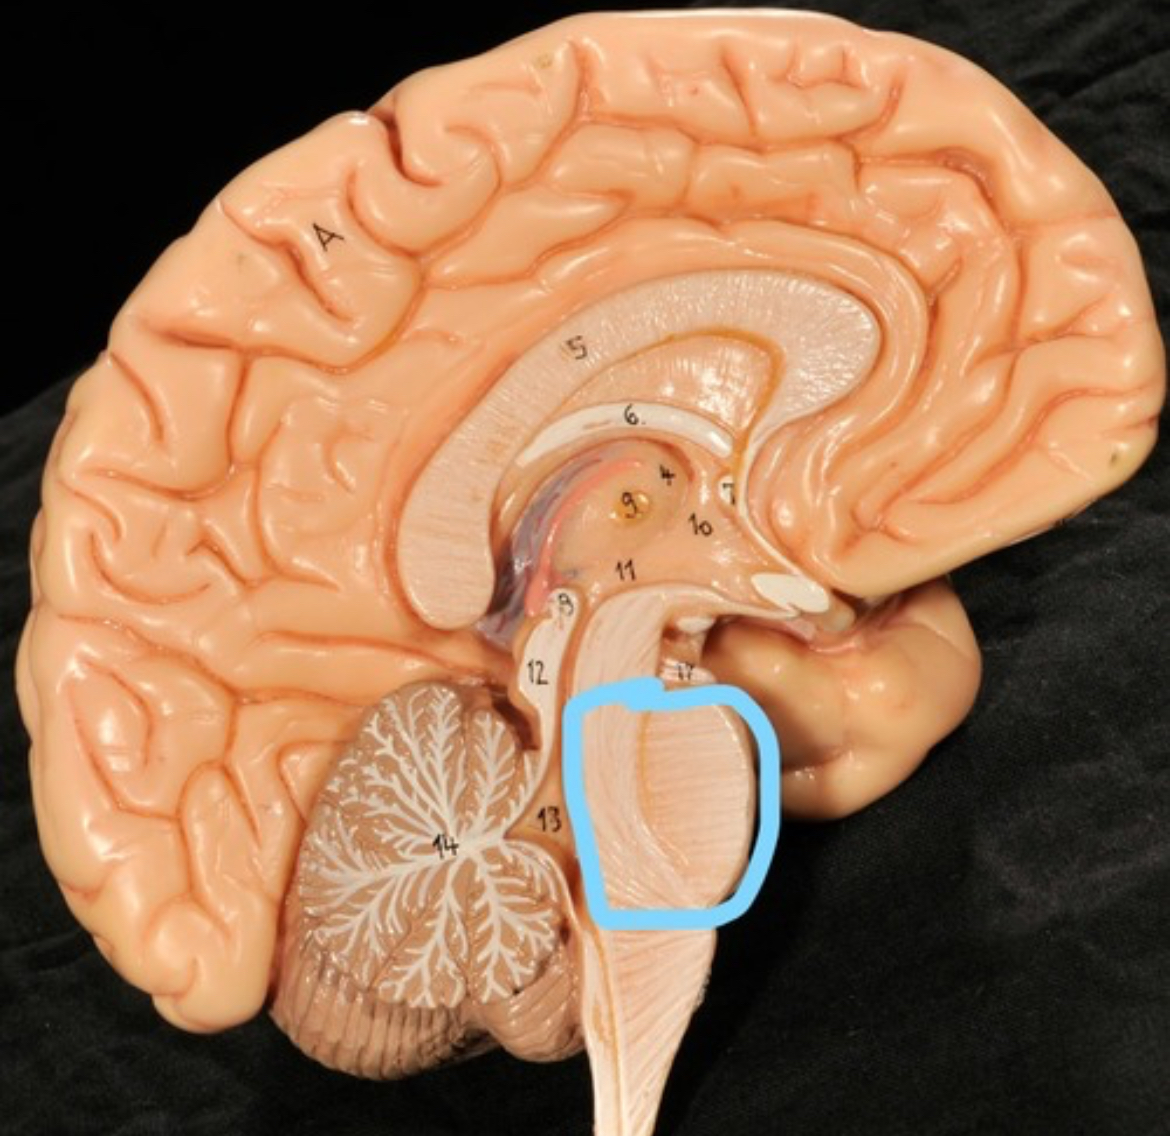

Pons

Medulla oblongata

4th ventricle